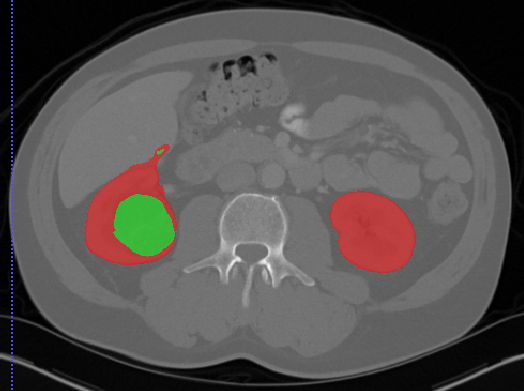

Edge-Aware 3D Image Segmentation Networks

[91]: Automated segmentation of kidneys and kidney tumors is an important step in quantifying the tumor’s morphometrical details to monitor the progression of the disease and accurately compare decisions regarding the kidney tumor treatment. Manual delineation techniques are often tedious, error-prone and require expert knowledge for creating unambiguous representation of kidneys and kidney tumors segmentation. We propose a 3D end-to-end edge-aware FCN for reliable kidney and kidney tumor semantic segmentation from arterial phase abdominal 3D CT scans. Our segmentation network consists of an encoder-decoder architecture that specifically accounts for organ and tumor semantics. We evaluate our model on the 2019 MICCAI KiTS Kidney Tumor Segmentation Challenge dataset. -

Furthermore, we extend our methodology and propose 3D boundary-aware FCNs for end-to-end and reliable semantic segmentation of kidneys and kidney tumor by encoding the information of edges in a dedicated stream that is supervised by edge-aware losses.

As is illustrated in Figure 2, our network consists of the main segmentation branch and the additional boundary stream that processes the feature maps at the boundary level. The main branch, following [90], is an asymmetric encoder-decoder structure. The input to the encoder is a crop which is initially fed into a convolution with 16 filters. Feature maps are then extracted at each resolution by feeding them into a residual block followed by a strided convolution (for downsizing and doubling of the feature dimension).

The bottom of the encoder entails four consecutive residual blocks that are connected to the decoder. The extracted feature maps in the decoder are upsampled using bilinear interpolation and added with feature maps from the encoder. The output of the decoder is concatenated with the output of the boundary and fed into a convolution with 2 channels where channel-wise sigmoid activation determines the probability of each voxel belonging to kidneys and tumor or only tumor classes.